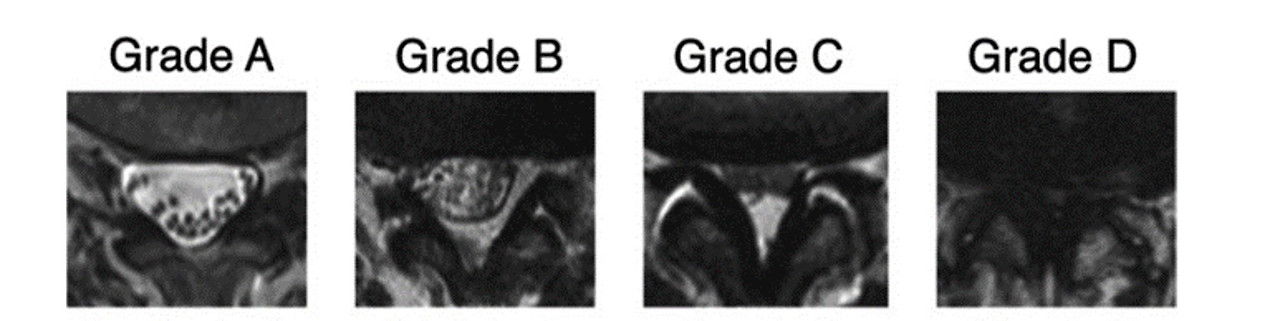

Grade A: 타원형의 경막 신경주 머니에 개개의 신경들이 점점이 흩어져 있다. 거의 정상 또는 아주 초기의 상태.

Grade B: 경막 신경주 머니에 물 반 고기반처럼 신경들이 조금 모여 있다. 그래도 신경들은 서로 구분된다.

Grade C: 개개의 신경들이 압축되어 하나의 덩어리로 보이면 말기로 가는 길목이다.

Grade D: 말기 협착증으로 수술이 필요한 상태이다.

만일 Grade A (1기) 또는 B (2기)에 해당한다면 일단 안심하고 약 처방을 받거나 신경주사치료를 하면 대개 잘 치료가 된다. Grade C (3기)에 해당한다면 적극적인 시술을 해볼 수 있겠지만 수술을 고려하는 것이 좋다. 물론 Grade D (4기)에 해당한다면 대학병원 척추 교수를 찾아가서 수술 날짜를 잡는 게 좋겠다. 믿을 수 있는 의료진에게 합당한 수술을 받는다면 절대 위험하지 않다.